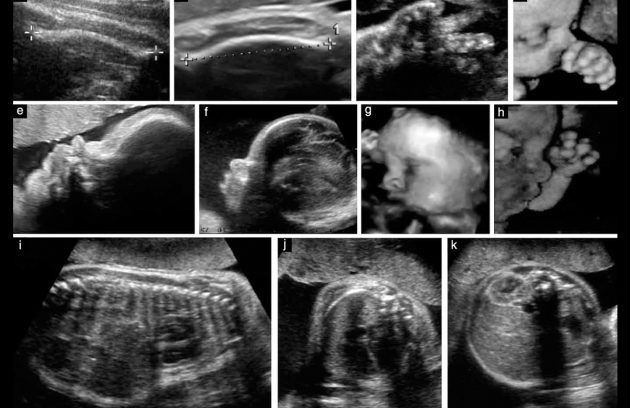

سونو بارداری در تهران پارس

سونو بارداری در تهران پارس سونو بارداری در تهران پارس | بهترین خدمات در سونوگرافی و رادیولوژی شرق بارداری یکی…